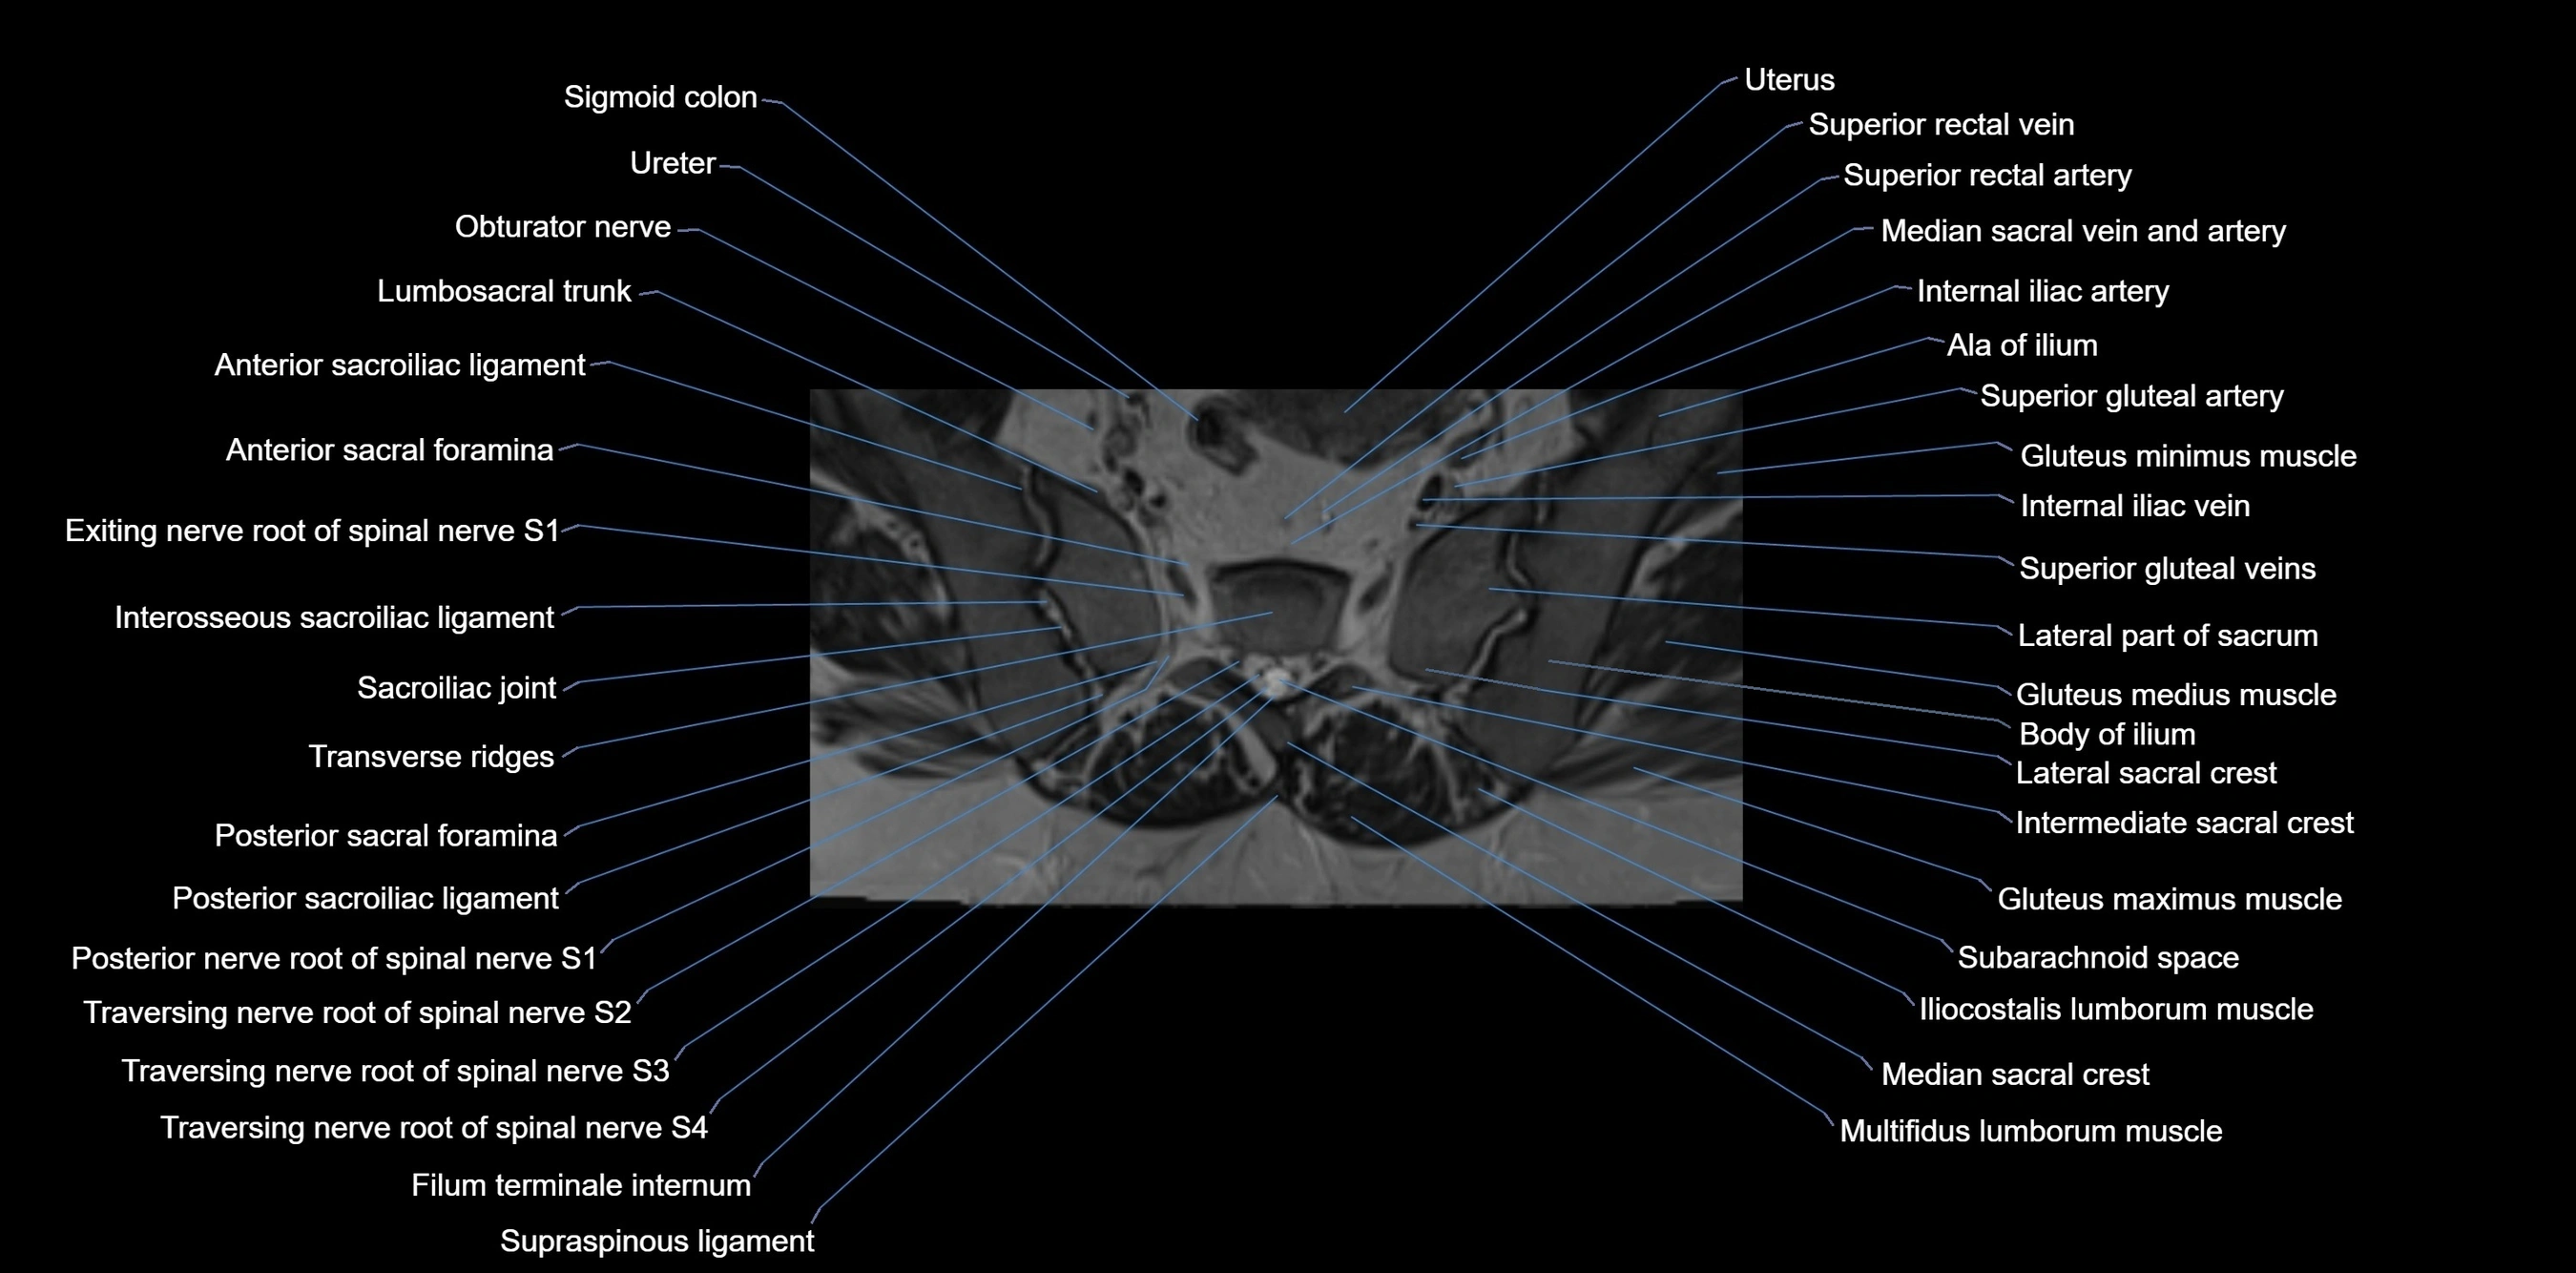

The ala of the ilium (iliac wing) is the large, expanded superior part of the ilium, forming the broad, fan-shaped lateral surface of the hip bone. It extends from the iliac crest superiorly to the arcuate line inferiorly and contributes significantly to the bony pelvis. Its external (gluteal) surface, internal (iliac fossa) surface, and iliac crest provide major muscular and ligamentous attachments, making it essential for pelvic stability and lower limb movement.

The external surface (gluteal surface) bears three rough curved lines (posterior, anterior, and inferior gluteal lines), which mark the origins of the gluteus maximus, medius, and minimus muscles. The internal surface (iliac fossa) provides attachment to the iliacus muscle and forms part of the lateral wall of the pelvic cavity. Posteriorly, the auricular surface articulates with the sacrum at the sacroiliac joint. The iliac crest forms the superior border, serving as a palpable surface landmark in clinical practice.

The ala of the ilium plays a central role in transmitting weight from the axial skeleton to the lower limbs and provides broad surfaces for muscle attachment, aiding in locomotion, posture, and abdominal wall support.